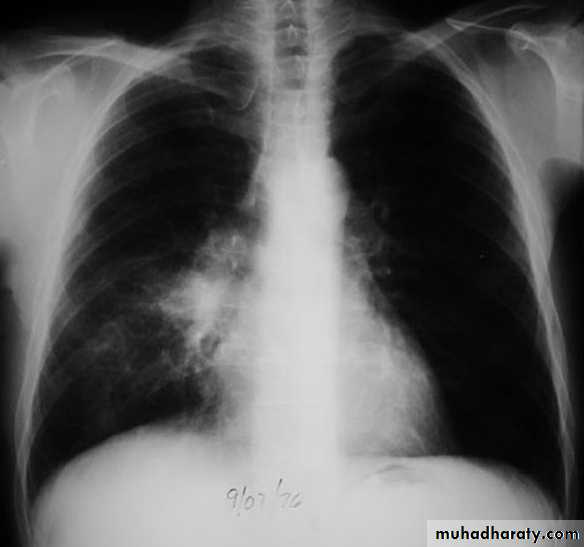

Massive pleural effusion with mediastinal shift to the left.

(A) Chest radiograph(B) CT coronal reconstruction. A massive effusion displaces the mediastinum to the left. CT shows the important pleural effusion together with the enhanced atelectatic left lung.

Note also the depression of the right hemidiaphragm (arrows).